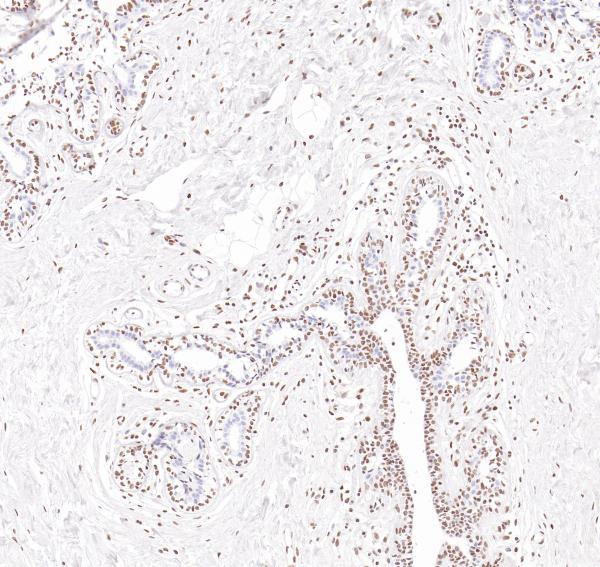

Estrogen Receptor α

BP6026

BP6139